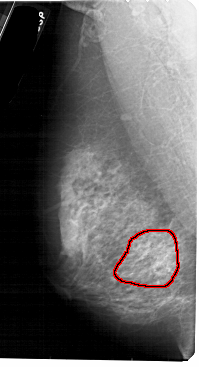

FILE: A_1885_1.LEFT_MLO.OVERLAY

TOTAL_ABNORMALITIES 1

ABNORMALITY 1

LESION_TYPE CALCIFICATION TYPE PLEOMORPHIC DISTRIBUTION SEGMENTAL

ASSESSMENT 4

SUBTLETY 2

PATHOLOGY BENIGN

TOTAL_OUTLINES 1

BOUNDARY

A_1885_1.LEFT_MLO

LEFT_MLO LINES 5491 PIXELS_PER_LINE 2971 BITS_PER_PIXEL 12 RESOLUTION 43.5 OVERLAY